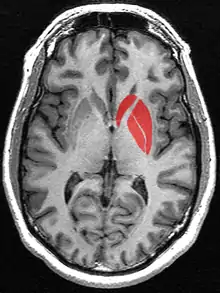

The striatum, or corpus striatum[5] (also called the striate nucleus), is a nucleus (a cluster of neurons) in the subcortical basal ganglia of the forebrain. The striatum is a critical component of the motor and reward systems; receives glutamatergic and dopaminergic inputs from different sources; and serves as the primary input to the rest of the basal ganglia.

Functionally, the striatum coordinates multiple aspects of cognition, including both motor and action planning, decision-making, motivation, reinforcement, and reward perception.[2][3][4] The striatum is made up of the caudate nucleus and the lentiform nucleus.[6][7] The lentiform nucleus is made up of the larger putamen, and the smaller globus pallidus.[8]

In primates, the striatum is divided into a ventral striatum, and a dorsal striatum, subdivisions that are based upon function and connections. The ventral striatum consists of the nucleus accumbens and the olfactory tubercle. The dorsal striatum consists of the caudate nucleus and the putamen. A white matter, nerve tract (the internal capsule) in the dorsal striatum separates the caudate nucleus and the putamen.[4] Anatomically, the term striatum describes its striped (striated) appearance of grey-and-white matter.[9]

The striatum is the largest structure of the basal ganglia. The striatum is divided into a ventral and a dorsal subdivision, based upon function and connections.